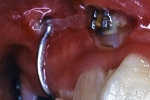

最良の解決策は、口腔外科的に開窓後、矯正歯科的に牽引し咬合に参加させることである。単に萌出させたと言うだけでなく、牽引後マルチブラケット装置を使用し、正常咬合を確立したケースの提示が求められている。

治療中